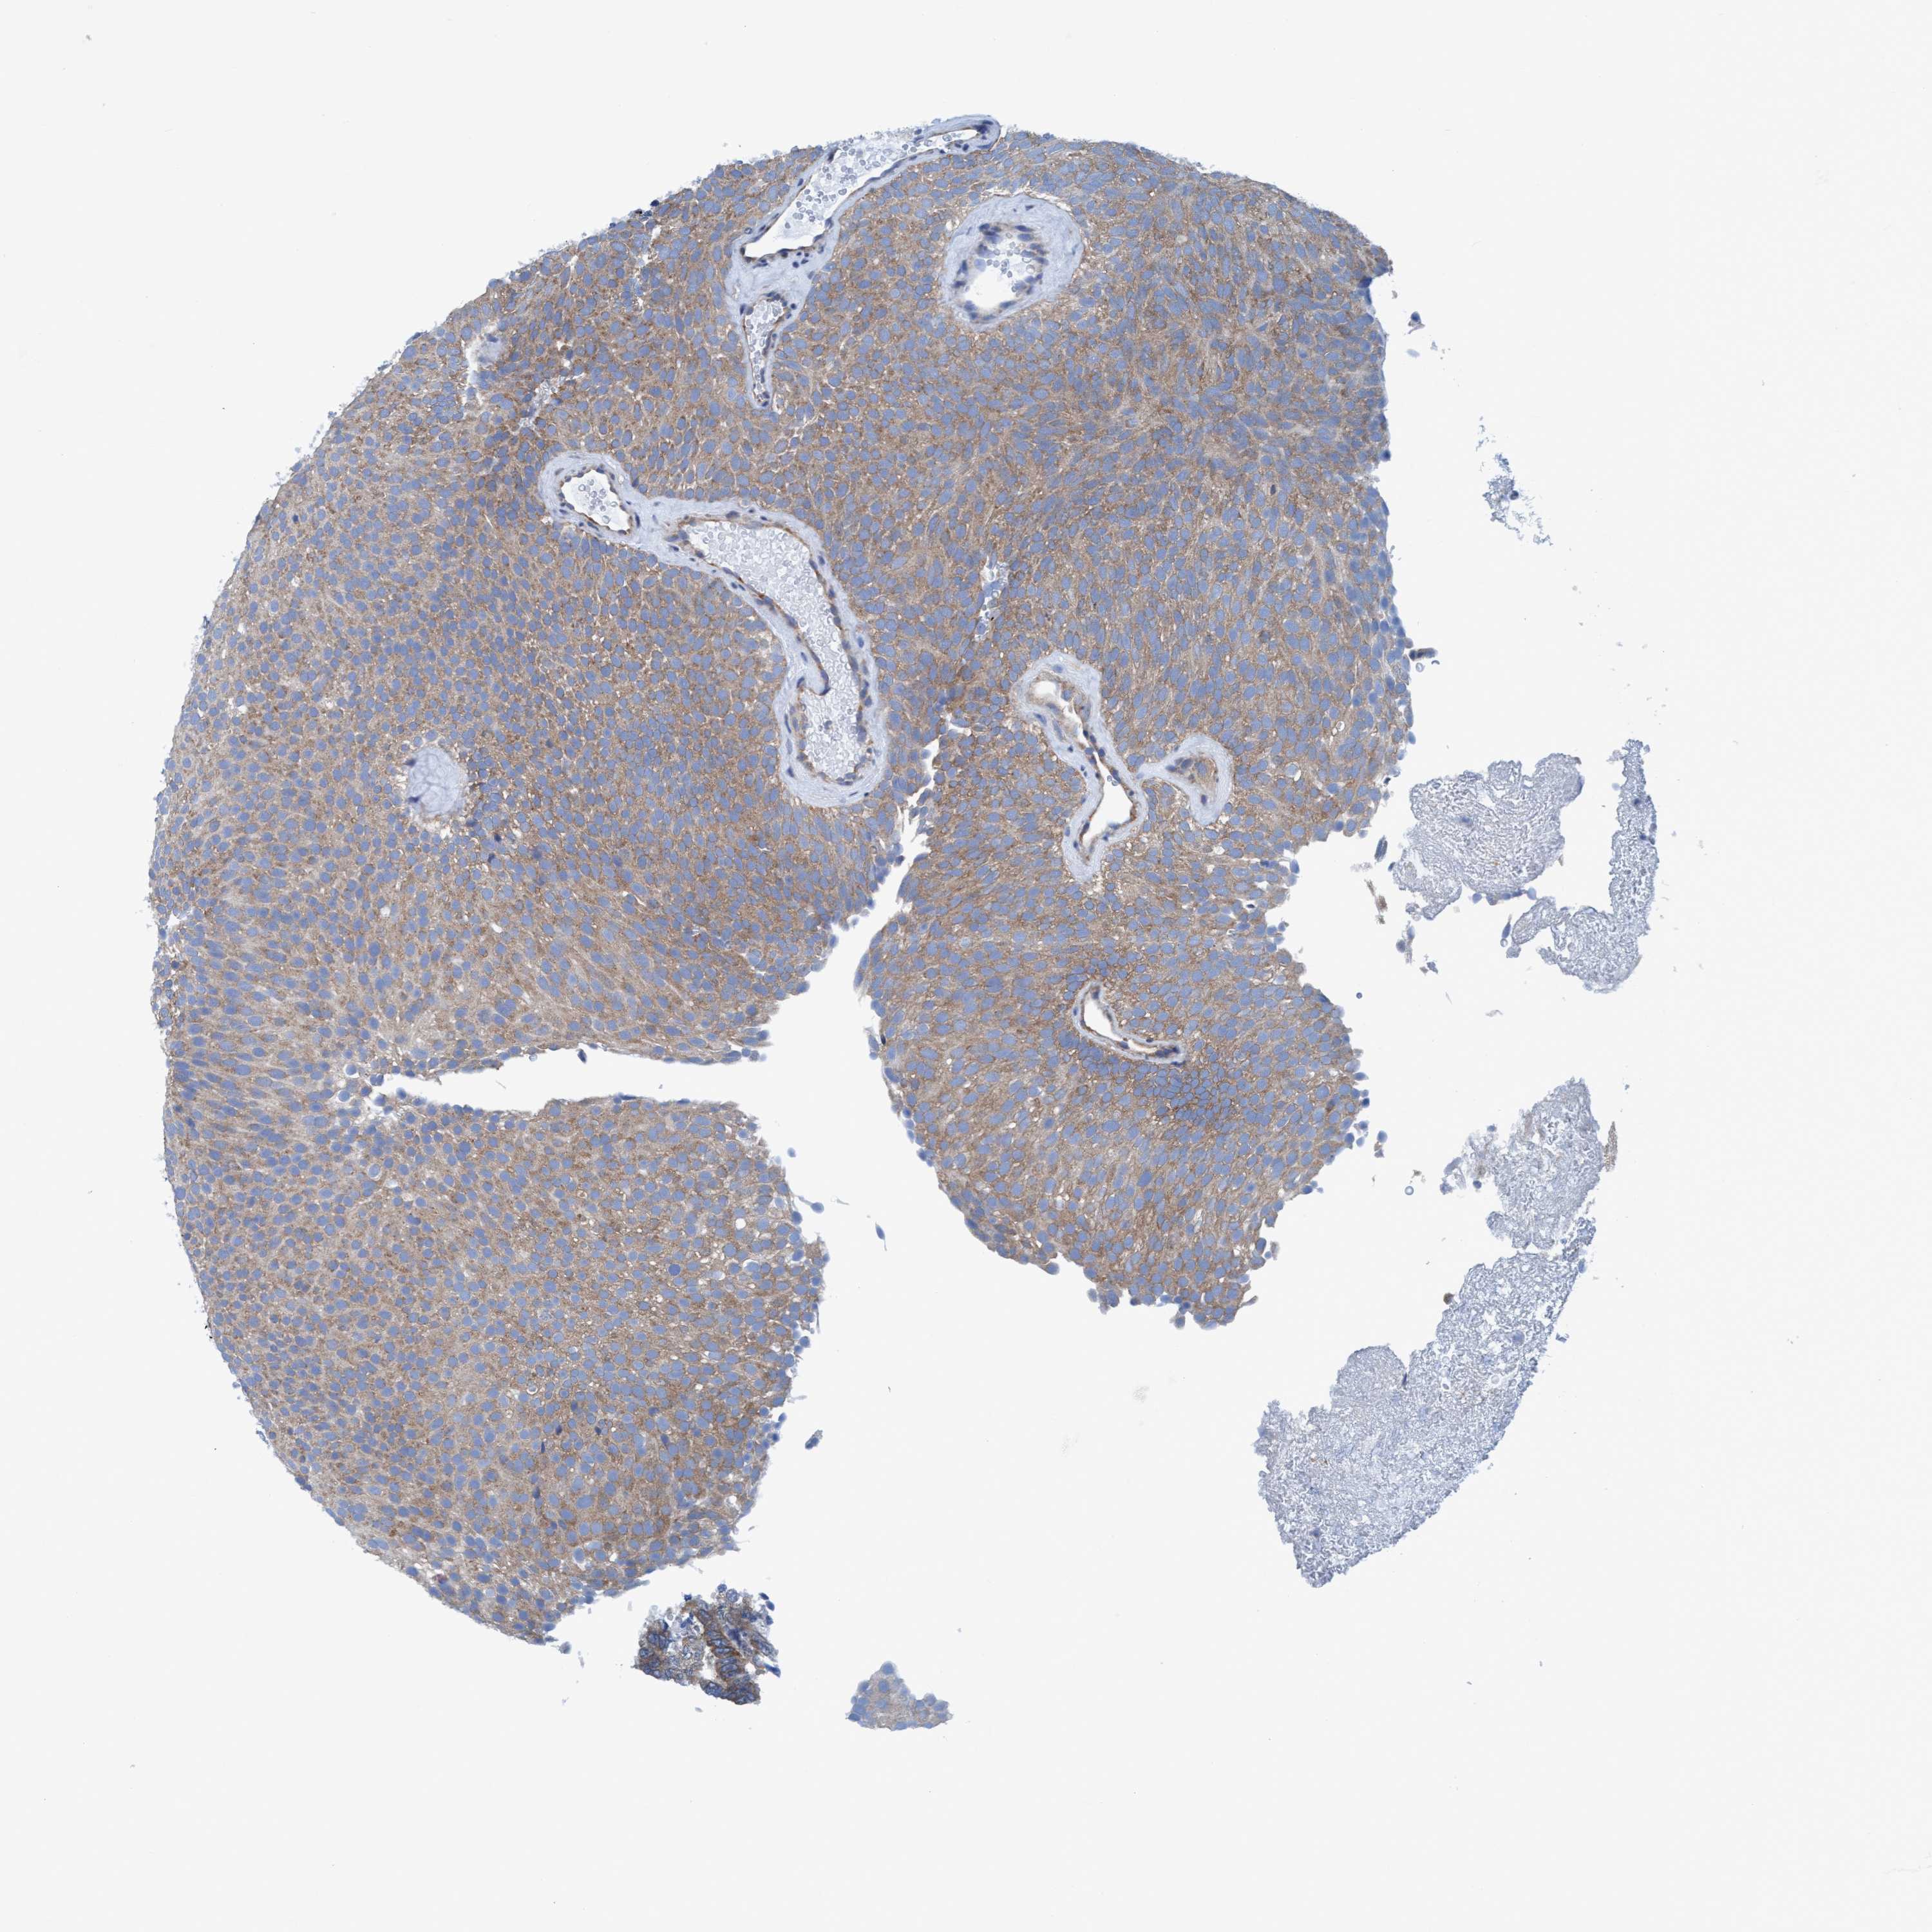

UROTHELIAL CANCER - Protein expressioni

A mouse-over function shows sample information and annotation data. Click on an image to view it in a full screen mode. Samples can be filtered based on level of antibody staining by selecting one or several of the following categories: high, medium, low and not detected. The assay and annotation is described here.

Antibody stainingi

Antibody staining in the annotated cell types in the current human tissue is reported as not detected, low, medium, or high, based on conventional immunohistochemistry profiling in selected tissues. This score is based on the combination of the staining intensity and fraction of stained cells.

Each image is clickable and will lead to virtual microscopy that enables deeper exploration of all samples and also displays staining intensity scores, fraction scores and subcellular localization as well as patient and tissue information for each sample.

Antibody HPA022949

Antibody HPA022963

Staining

High

Medium

Low

Not detected

Intensity

Strong

Moderate

Weak

Negative

Quantity

>75%

75%-25%

<25%

None

Location

Nuclear

Cytoplasmic/membranous

Cytoplasmic/membranous,nuclear

Urothelial carcinoma, Low grade

Urothelial carcinoma, High grade